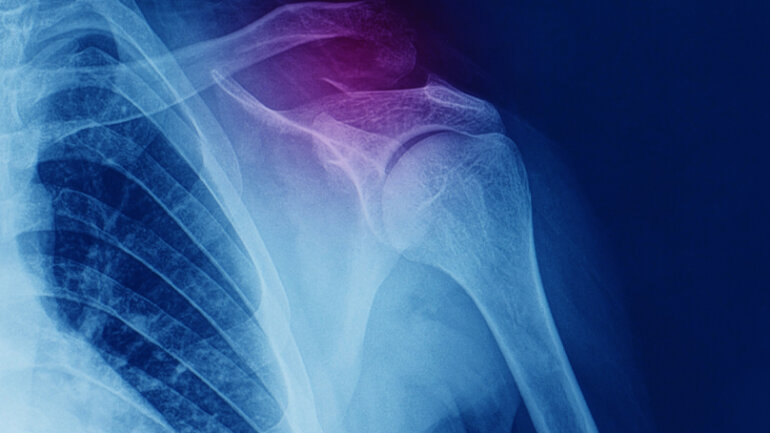

Ο περιορισμός βάδισης αυξάνει τον κίνδυνο κατάγματος

Ο περιορισμός στο περπάτημα σχετίζεται σημαντικά με τον κίνδυνο κατάγματος σε μια διάρκεια 4-5 ετών, σύμφωνα με μια μελέτη που δημοσιεύθηκε στο JAMA Network Open.